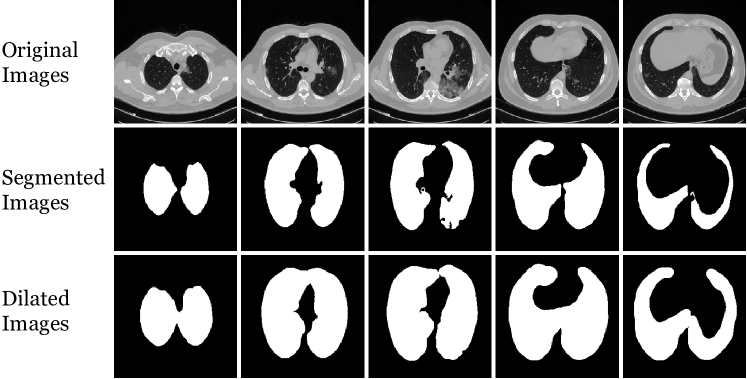

Lung segmentation is applied to individual slices in the CT volume. The output for each slice is the corresponding binary segmentation mask, separating lung areas (including air pockets, tumors and effusions in lung regions) from background or other organs, as shown in Figure 3. The segmentation extracts left and right lungs separately, although this information is not used in our model.

Lung segmentation with U-Net is very successful, as reported in [31] and also observed in our case. Nonetheless, in order not to miss infected regions, we dilated the masks with a 10-pixel structuring disk. Sample slices from the IST-C dataset and corresponding lung masks obtained by U-Net and the dilated masks are shown in Figure 3.